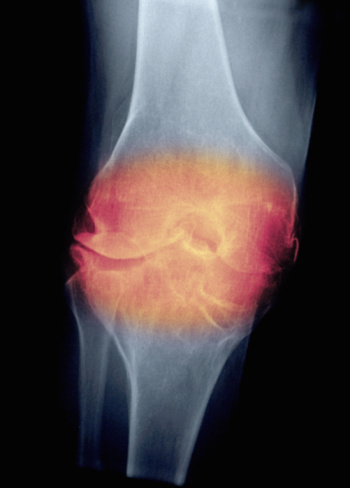

Артрит – это острое воспалительное заболевание суставов, часто поражающее также и околосуставные ткани. Сопровождается заболевание сильной болью, опухлостью сустава, изменением его внешнего вида (деформацией). Причинами возникновения артрита могут быть инфекционные заболевания вирусной, бактериальной или грибковой этиологии, нарушение обмена веществ (подагра), сбои в иммунной системе, гормональные нарушения, травмы, переохлаждения, неправильное питание, бедное на витамины и микроэлементы. Развивается артрит как у людей после 40 лет, так и в более молодом возрасте. Если заболевание вовремя не выявить и не приступить к его лечению, возможно развитие артроза или сепсис, а также поражения внутренних органов – почек, мочевого пузыря, печени, сердца.